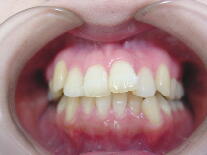

症例1 (10代 女性) 左右上下顎第一小臼歯抜歯例

初診時